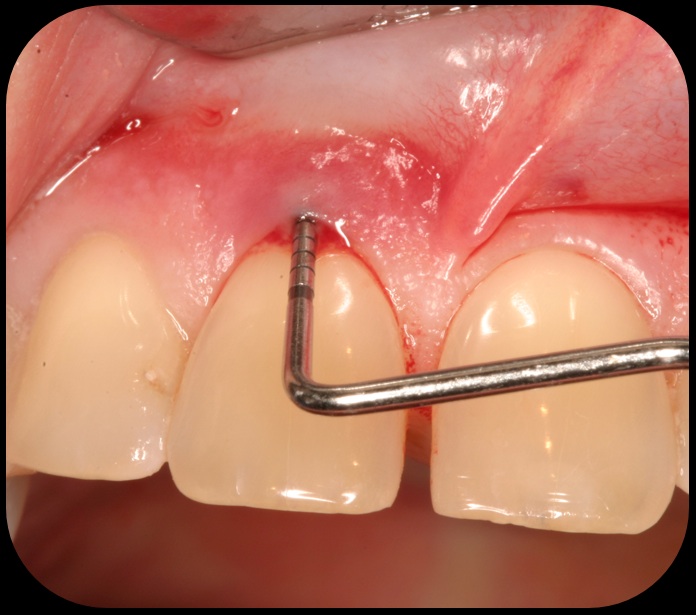

Severe periodontitis lesion.

Fig. 2

Facial bone loss and a mesial vertical defect.

Fig. 3

Evidence of clinical attachment gain.

Fig. 6

The 9-year postoperative radiograph.

Fig. 7